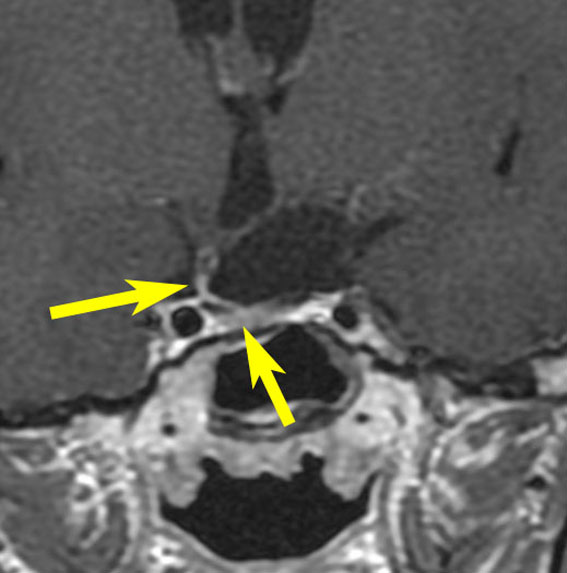

矢印の先に見えるように下垂体は正常の形態です。この画像から灰白隆起の左後方,乳頭体の前方が腫瘍発生母地ということがわかります。尿崩症もなく下垂体機能は正常です。経鼻的な内視鏡手術で腫瘍の大部分を摘出すれば下垂体機能は廃絶します。

とにかく失明を避けるために急いで経蝶形骨洞手術(transsphenoidal-transtuberculum sellae approach)で腫瘍のう胞の減圧をしました(緑の矢印の経路 by 函館中央病院加藤功先生)。その後に前頭開頭で腫瘍を全摘出しました(右側の画像)。尿崩症はでましたが下垂体前葉機能は正常です。

右視力 0.45,左明暗弁の視力が残りました。でももし,経鼻手術をしないでいきなり開頭すればおそらく全盲になっていた例です。